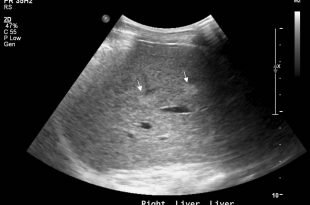

Анатомия и строение печени

Печень — важный, с точки зрения выполнения возложенных функций, орган в человеческом организме. Для этого одна из самых крупных желез отличается особым строением. Состоит орган из капсулы (внешней оболочки), паренхимы (печеночной ткани) и гепатоцитов (желчевырабатывающих клеток). Все элементы печени, включая сосуды, протоки, правую и левую дольки, тесно связаны с ближайшими подобными структурными единицами, где-то сливаясь в крупные, а где-то разделяясь на меньшие. Расположена печень в правом подреберье и практически полностью защищена брюшиной. Месторасположение органа фиксировано благодаря связочному аппарату, поддерживающему печень в одном положении. Особое кровоснабжение печени, обеспеченное прохождение больших объемов венозной крови, чем артериальной, обеспечивает очистку всего кровотока.